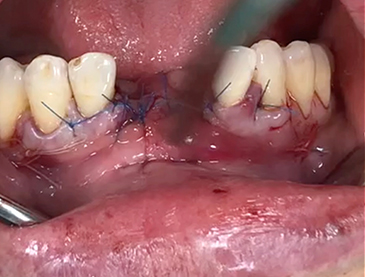

A clinical case using resorbable membrane

• A clinical case using resorbable membrane 1